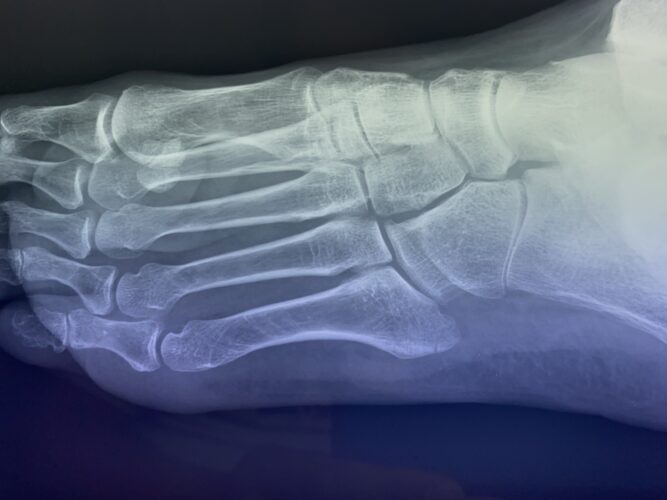

第5中足骨基底部骨折でお悩みの方へ(下駄骨折)の総合ガイド|当院が実践す…

第5中足骨骨折の1症例について